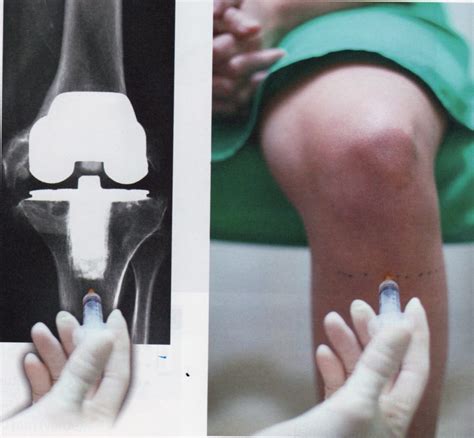

Cuanto Dura Una Protesis De Rodilla, ¿Cuánto tiempo dura una prótesis de rodilla Todo lo que debes saber, 6.64 MB, 04:50, 119,988, Top Doctors LATAM, 2017-08-23T17:42:43.000000Z, 3, SALUTARIS MEDICAL CENTER: Prótesis total de rodilla, salutarismedicalcenter.blogspot.com, 1600 x 721, jpeg, WebLa mayoría de las articulaciones de la rodilla artificiales dura de 10 a 15 años. Algunas duran hasta 20 años antes de aflojarse y necesitar que las reemplacen de nuevo. Las. WebEl tiempo medio habitual de una baja laboral por prótesis de rodilla es de 6 a 12 semanas. Pacientes con trabajos menos demandantes pueden volver a trabajar tan pronto hagan. WebNormalmente, se pueden retomar las actividades cotidianas a las 3 o 6 semanas tras la cirugía. El programa de ejercicio físico de la recuperación en casa., 20, cuanto-dura-una-protesis-de-rodilla, Novedades y Muebles WebLa mayoría de las articulaciones de la rodilla artificiales dura de 10 a 15 años. Algunas duran hasta 20 años antes de aflojarse y necesitar que las reemplacen de nuevo. Las. WebEl tiempo medio habitual de una baja laboral por prótesis de rodilla es de 6 a 12 semanas. Pacientes con trabajos menos demandantes pueden volver a trabajar tan pronto hagan. WebNormalmente, se pueden retomar las actividades cotidianas a las 3 o 6 semanas tras la cirugía. El programa de ejercicio físico de la recuperación en casa.

WebPodemos concluir diciendo que, en líneas generales, la supervivencia de las prótesis de rodilla es de unos 15 años de media. Esto puede variar mucho en cada uno. WebEl tiempo de hospitalización después de la implantación de la prótesis de rodilla es de 3 a 5 días, aunque se exigirá al paciente que empiece a moverse prácticamente desde el.

WebLa supervivencia (o cuánto duran las prótesis de rodilla), según el especialista, Doctor Villanueva, incluso en pacientes jóvenes, pueden sobrevivir de 15 a 20 años, en el 90. WebEl tiempo que puede llevar colocar una prótesis de rodillas es de 60 a 90 minutos. Con el nuevo material de reemplazo de la rodilla, los componentes se. Web¿Cuánto dura una Prótesis de rodilla? Al igual que otros tipos de endoprótesis, una prótesis de rodilla tiene una vida útil limitada. Con una cirugía adecuada y sin complicaciones. WebUna cirugía de prótesis de rodilla no dura ni mucho ni poco, si no lo justo y necesario. La recuperación tras una operación de prótesis de rodilla puede ir de 4 a 6. WebEl 2 de octubre me sometieron a una protesis de rodilla als 12 dias juntlo mucho liquido me volvieron a meter al quirofano para hacer una limpieza por q teni. WebA los 50-60 los pacientes quieren vivir las actividades y el tipo de vida correspondiente a su edad y así sucesivamente. En general las prótesis de rodilla no tienen una duración.

WebEn principio, una cirugía primaria de rodilla debería durar entre una y dos horas, aunque pueden registrarse variaciones. Una vez el paciente ha sido anestesiado y el campo.